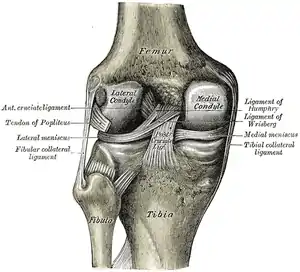

Anterior view of knee.

Knee joint. Deep dissection. Anterior view